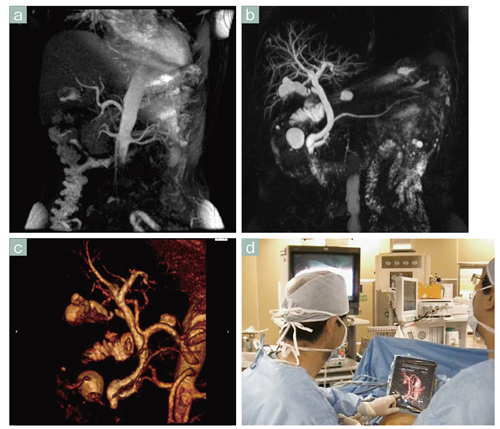

■症例1 Inhanceによる非造影MRA(胆嚢摘出術)

a:呼吸同期inflow IR法による腹腔動脈~肝動脈部のMIP像,b:MRCP画像。aとbを合成し,VR処理を行った(c)。dはcを用いた腹腔鏡下胆嚢摘出術の様子。iPadにて右肝動脈の位置を確認しながら手術を行っている。